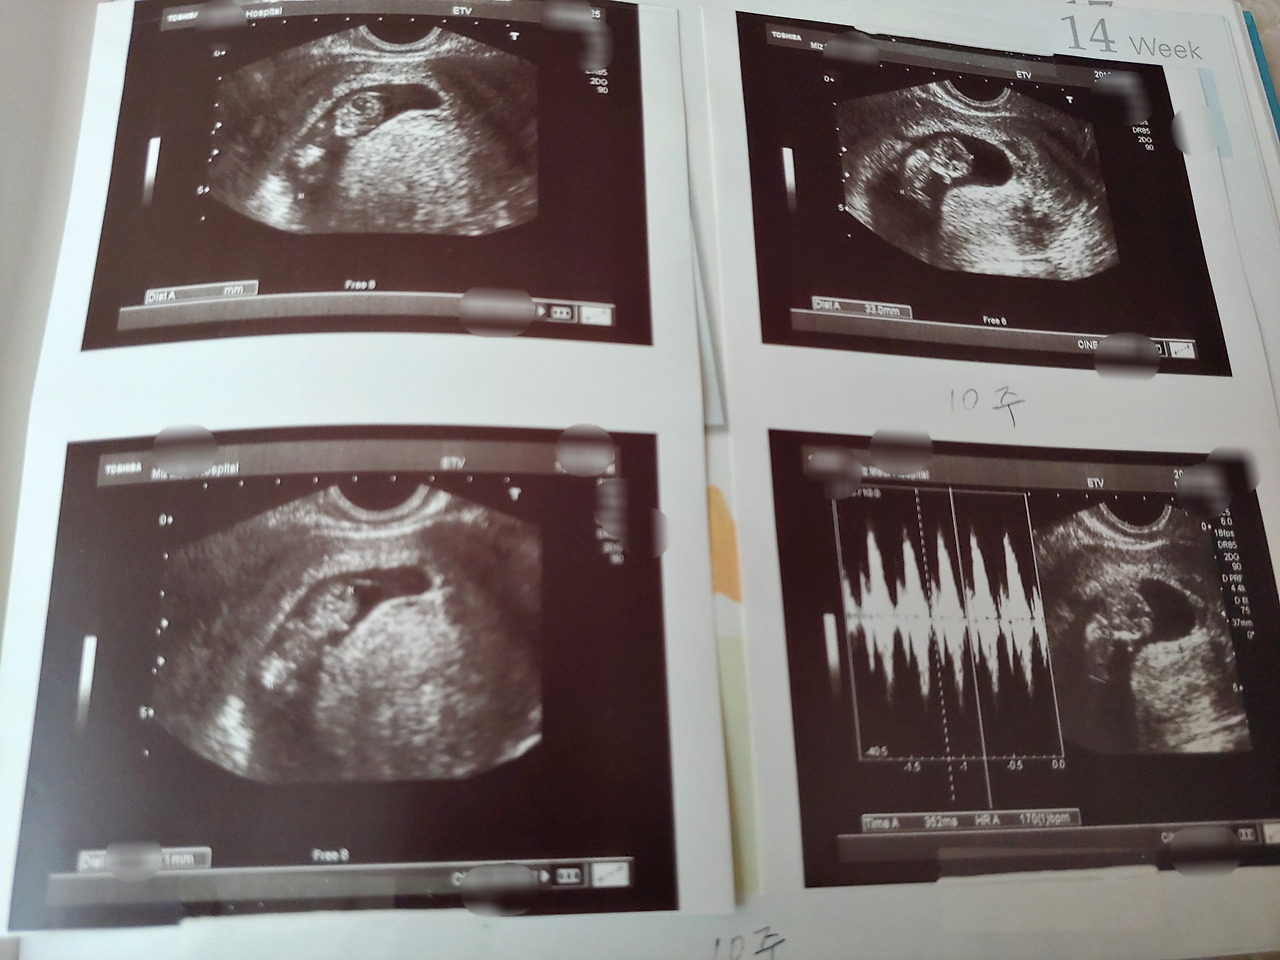

난임으로 6년 만에 6번 유산 끝에 마지막 시험관으로 첫째를 힘들게 만나고 다시 6년 후 둘째가 기적같이 자연임신으로 우리에게 왔다.

둘째는 배도 빨리 나오고 태동 느낌도 엄청 빨리 느껴졌다. 첫째는 임신 20주에 첫 태동을 느꼈는데 둘째는 임신 12주쯤에 지렁이 기어가는 느낌이 살짝 나더니 임신 15주에는 자주 '스윽스윽' 하는 느낌이 자주 들었다.